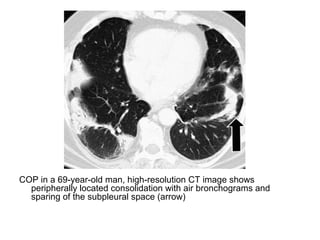

COP in a 69-year-old man, high-resolution CT image shows

peripherally located consolidation with air bronchograms and

sparing of the subpleural space (arrow)